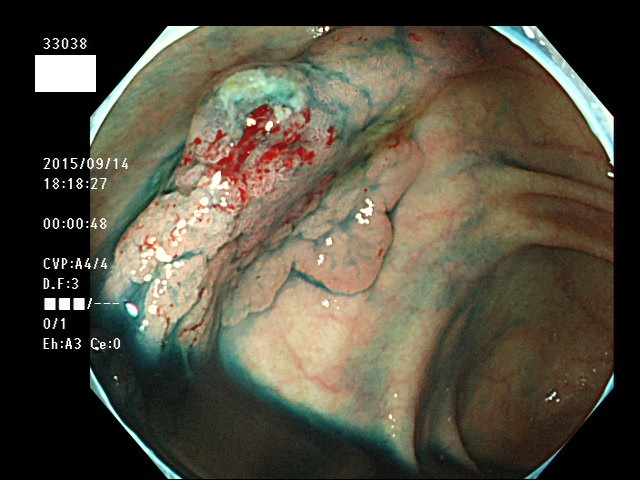

上記100名より抽出した平坦・陥凹型腺腫(=癌化の危険が高いが見落としやすい病変)の内視鏡写真

33003 33004 33005 33006 33007 33008 33009 33010 33011 33012 33013 33014 33015 13306 33018 33021 33024 33025 33026 33029 33030 33031 33032 33033 33036 33038 33039 33041 33042 33045 33046 33048 33051 33053 33054 33055 33057 33060 33063 33066 33068 33069 33071 33072 33074 33077 33078 33080 33086 33088 33089 33090 33091 33093 33095 33096 ・・・・・・の56名